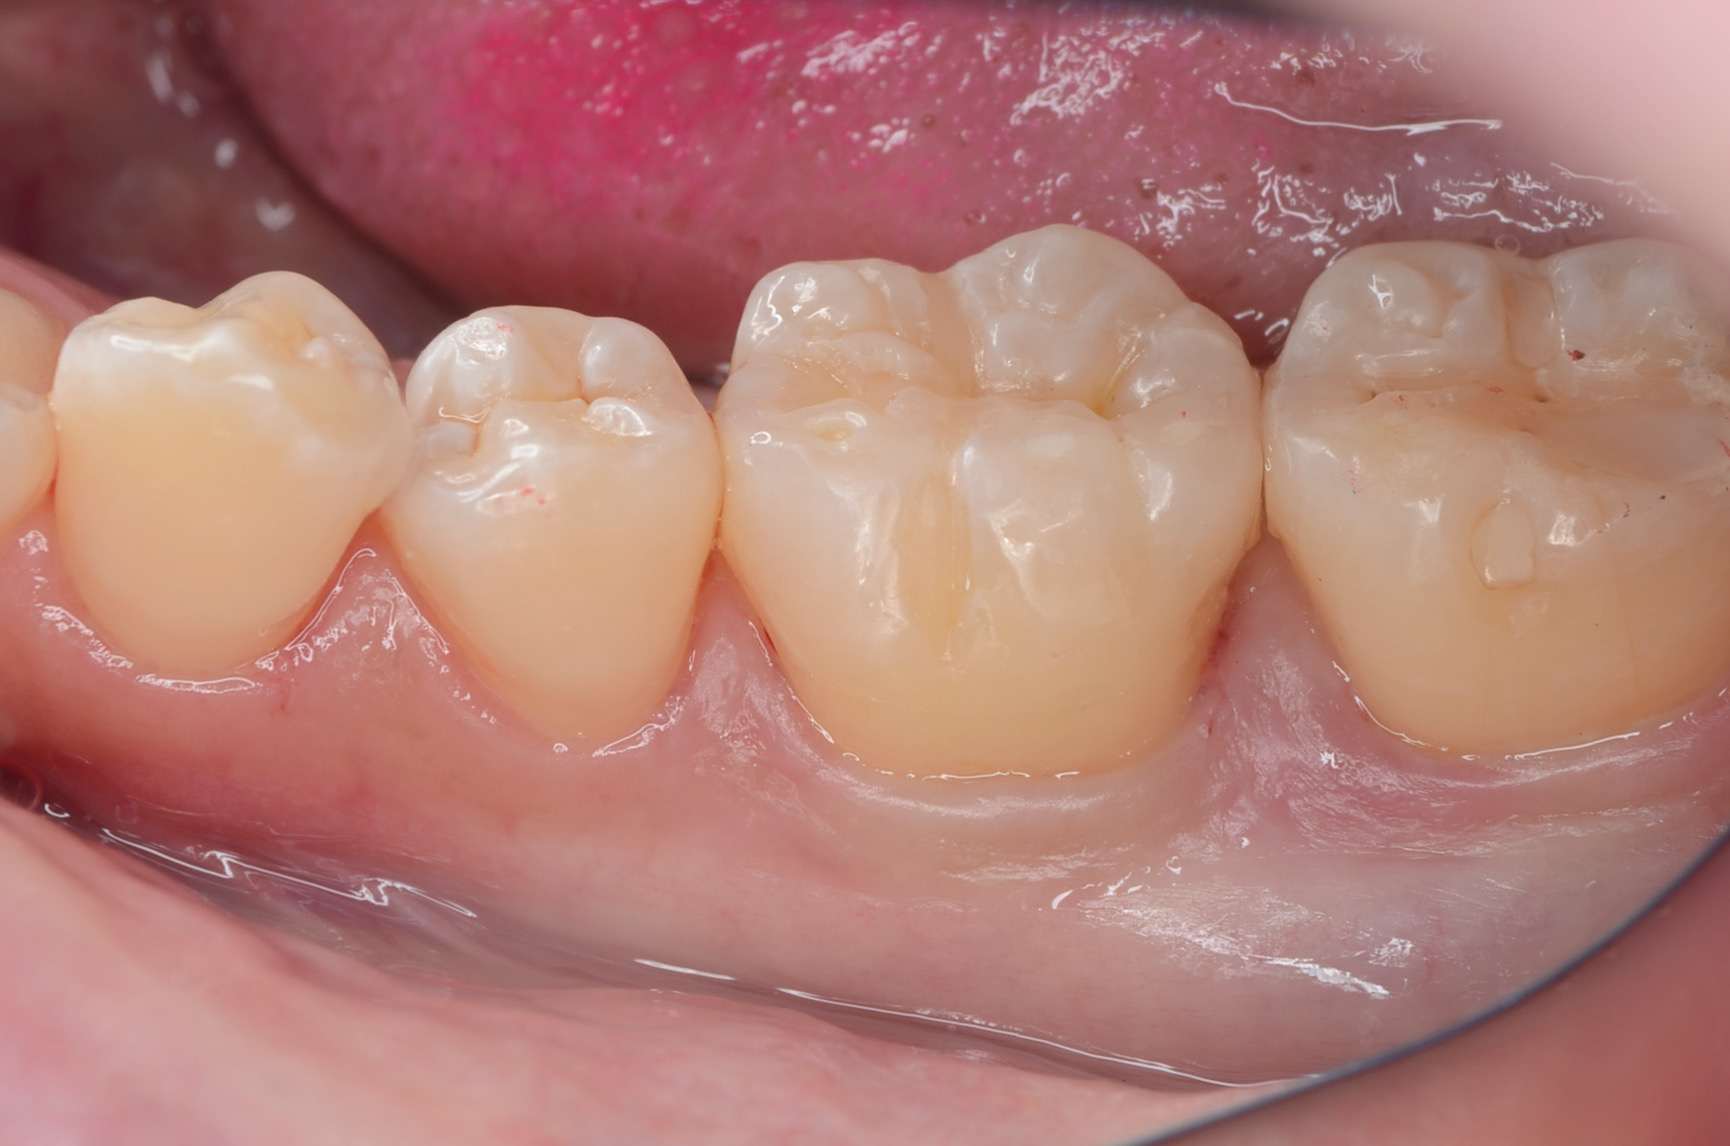

After

舌側面観